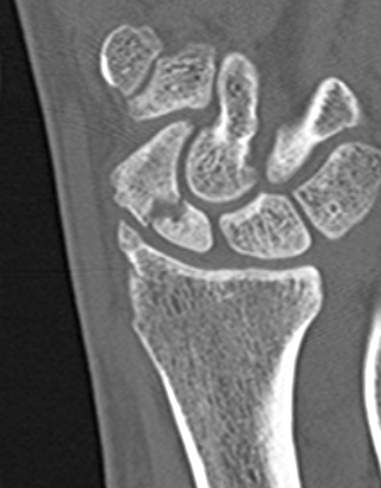

CT

Indication

- diagnose nonuion

- identify humpback deformity

- plan size and shape of bone graft

Failure of fracture to unite at 3 months on CT scan

Nonunion with flexion deformity